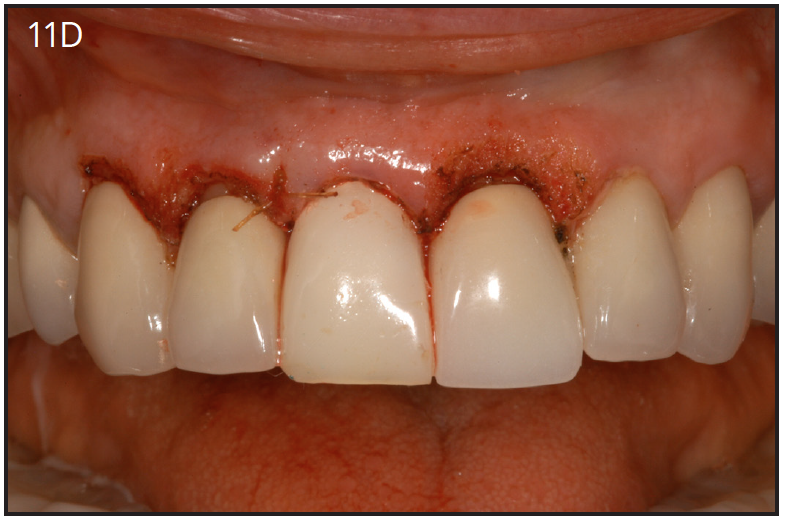

An implant most closely replicates the feel of a natural tooth. Once it is osseointegrated, many patients cannot differentiate an implant from a natural tooth. Furthermore, dental implants do not decay or need a root canal. Even though the cost is slightly more than a bridge, it is a great investment for the future, as implants usually last longer than a bridge. A 10-year report on posterior single implants shows a success rate of 97%.29 Once an implant is placed, an integration/healing time of approximately 4 months is necessary before final crown is placed. A temporary crown can be placed the same day the implant is placed. (Figures 11A-E)

Figure 11D – Immediate placement of temporary crown over the abutment; laser crown lengthening was performed on the adjacent teeth to improve gingival symmetry

Figure 11D